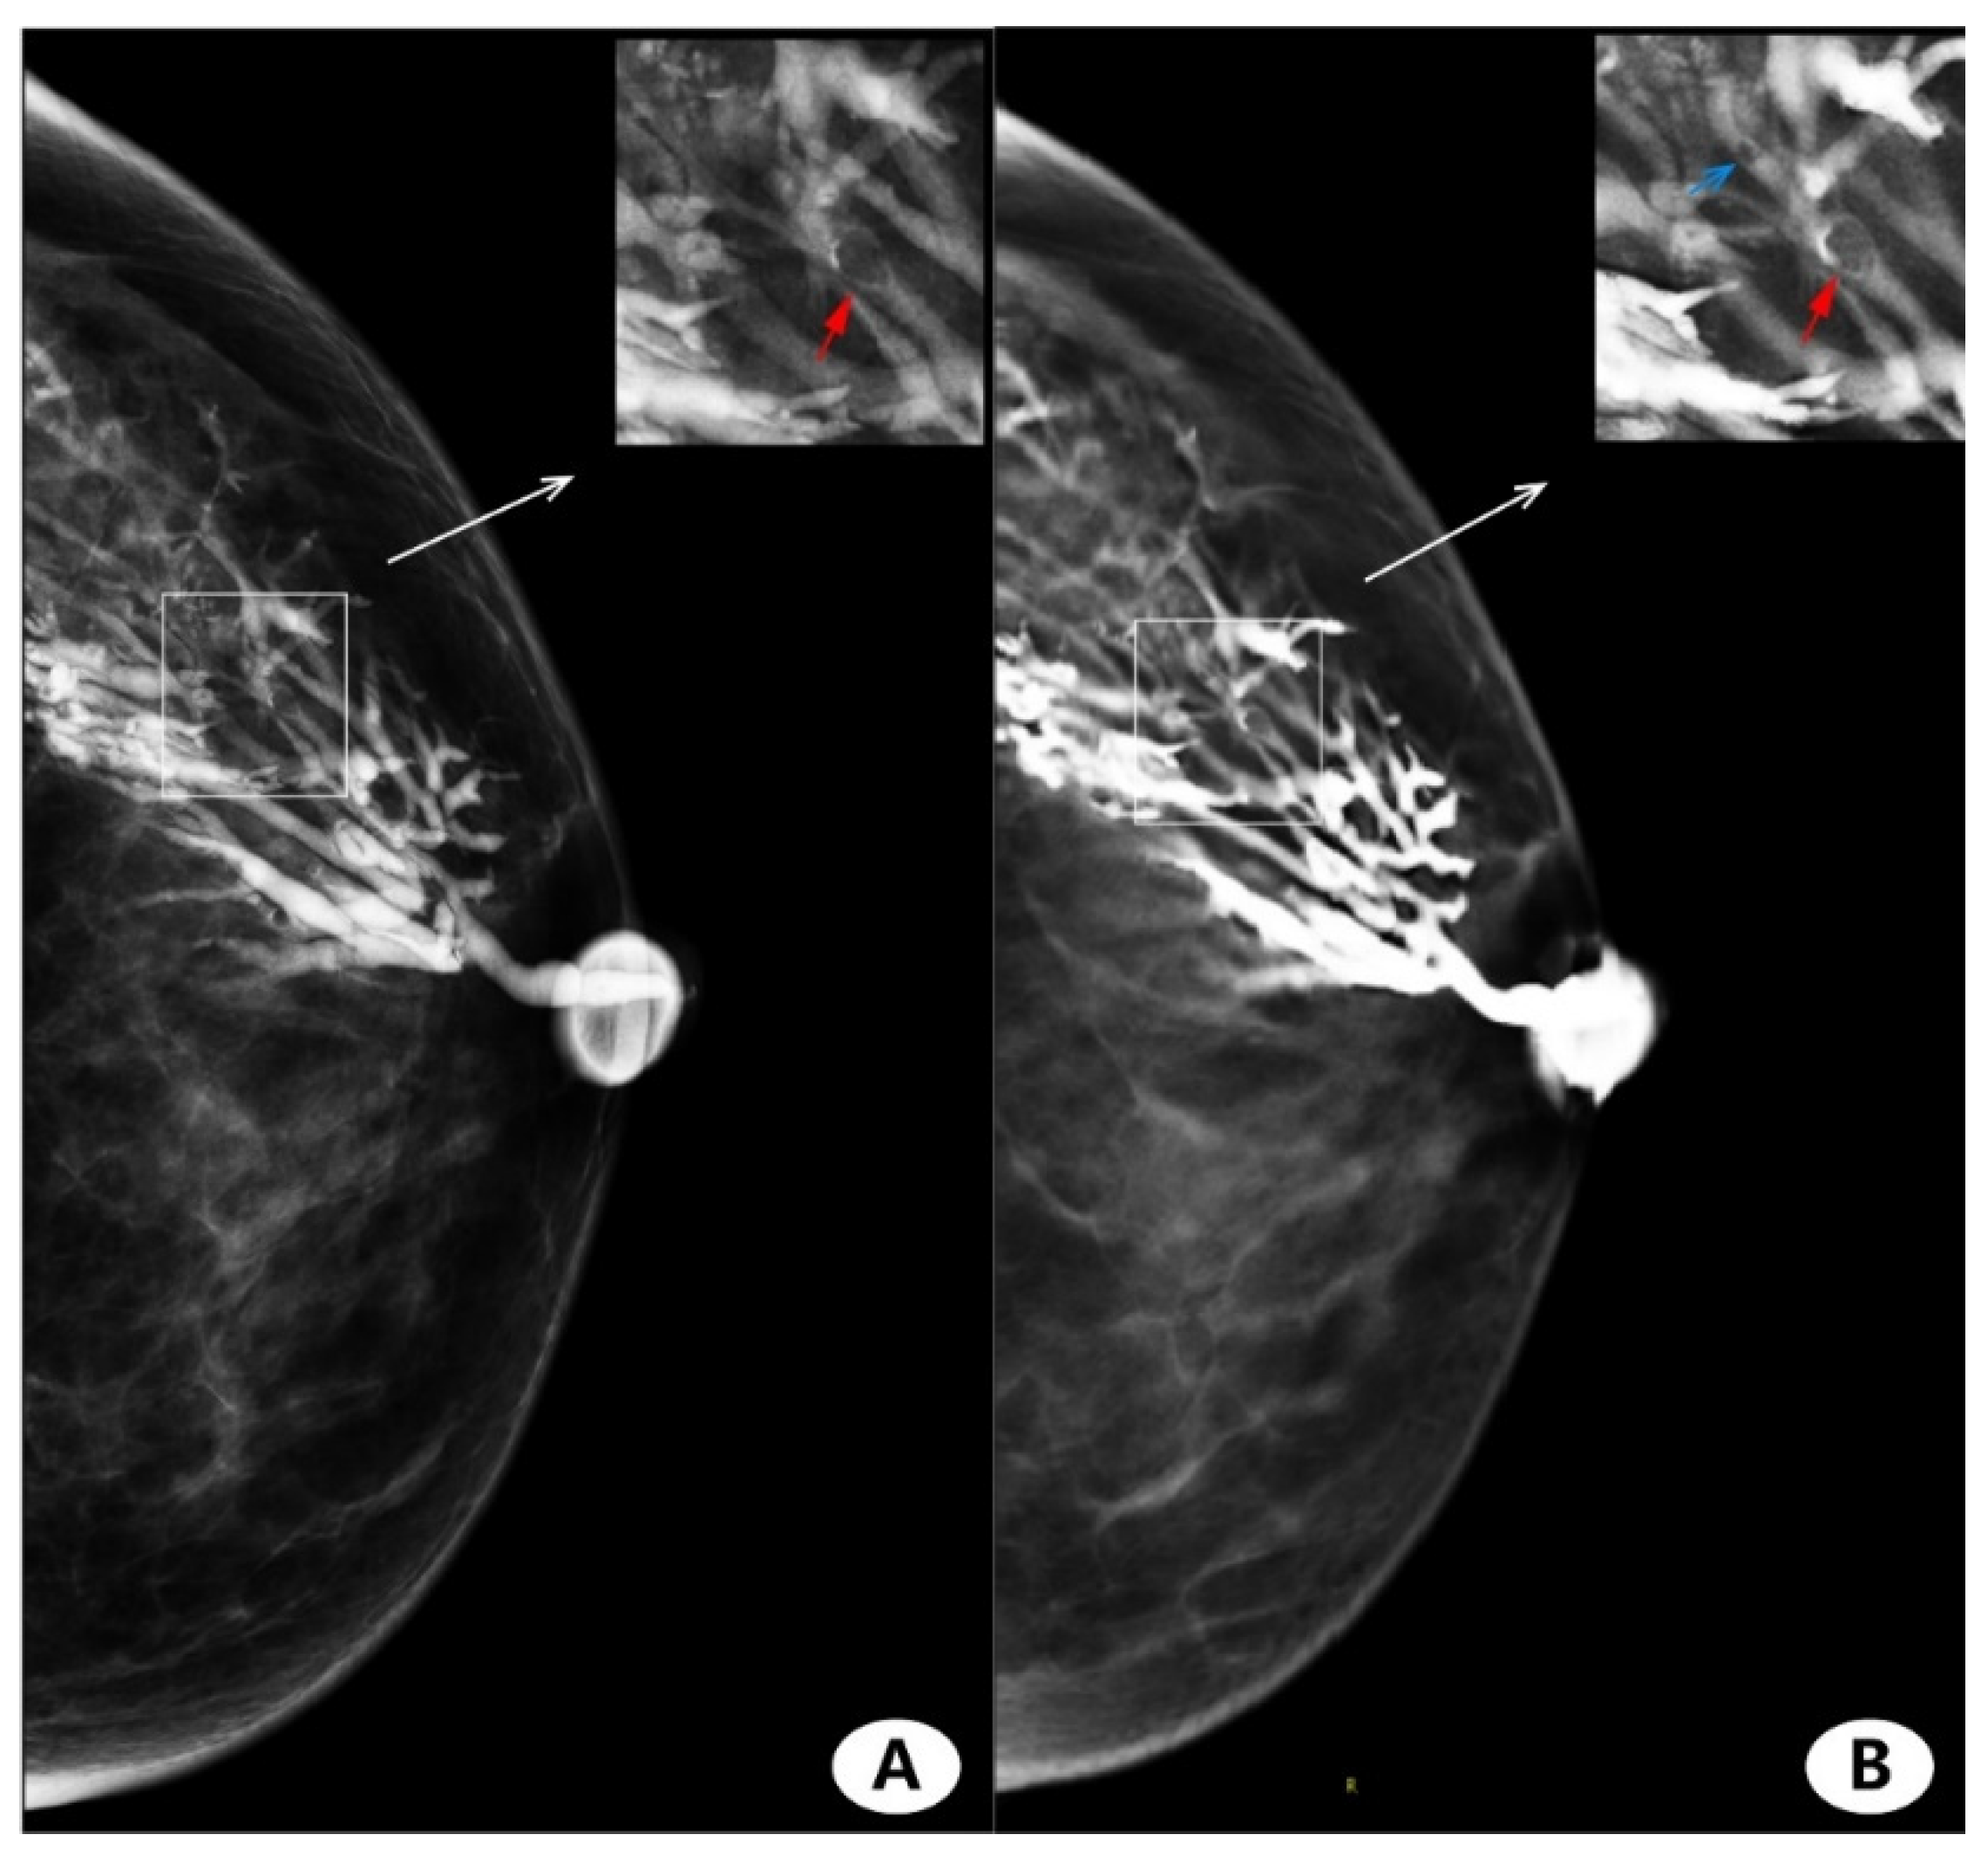

3.4. Imaging Finding